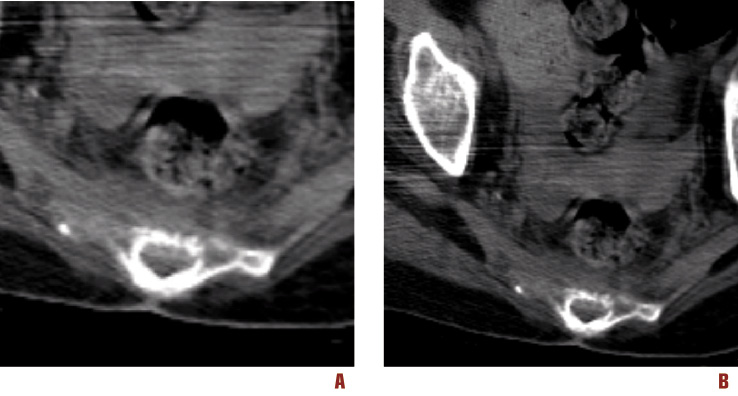

Figura 4. A e B. TC senza mezzo di contrasto che pongono in evidenza l’invasione del mesoretto

Si rendeva pertanto necessario proseguire l’iter diagnostico presso ambiente specialistico internistico-ematologico. Le Figure 1-4 mostrano le immagini della regione sacrale e del mesoretto ottenute mediante RM e TC.